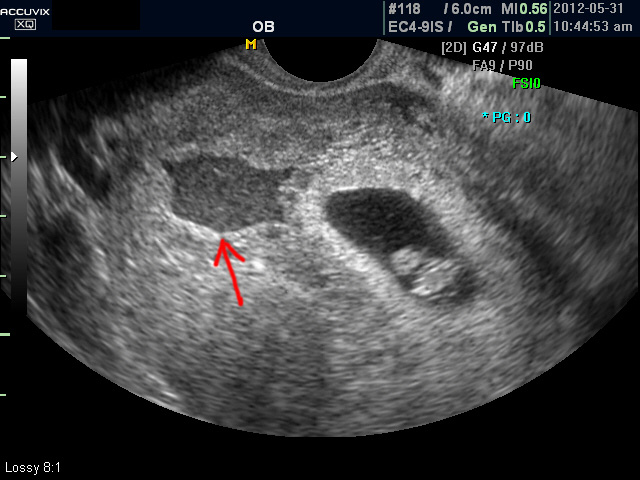

초음파 검사에서는 정상 임신으로 진단된 후 아기집 (태낭. G-Sac)이 보이지 않거나 평균 임신 주수에 비하여 아기집이 상당히 작을 때, 그리고 임신 8주 이후에 태아 심박동이 없는 경우에 유산일 가능성이 높다고 판단합니다.

아래는 유산과 관련된 초음파 사진으로 위 사진은 유산기가 있다고 하는 경우 (의학적으로는 절박유산)의 사진이고 아래의 사진은 고사 난자라고 하여 태아가 정상적으로 형성되지 못한 유산의 사례입니다.